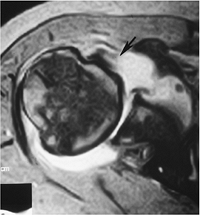

![]() |

FIGURE 7-35 Axial MR arthrogram image demonstrating a large posterior capsule with glenolabral separation (arrow) and a small paralabral cyst (open arrow).